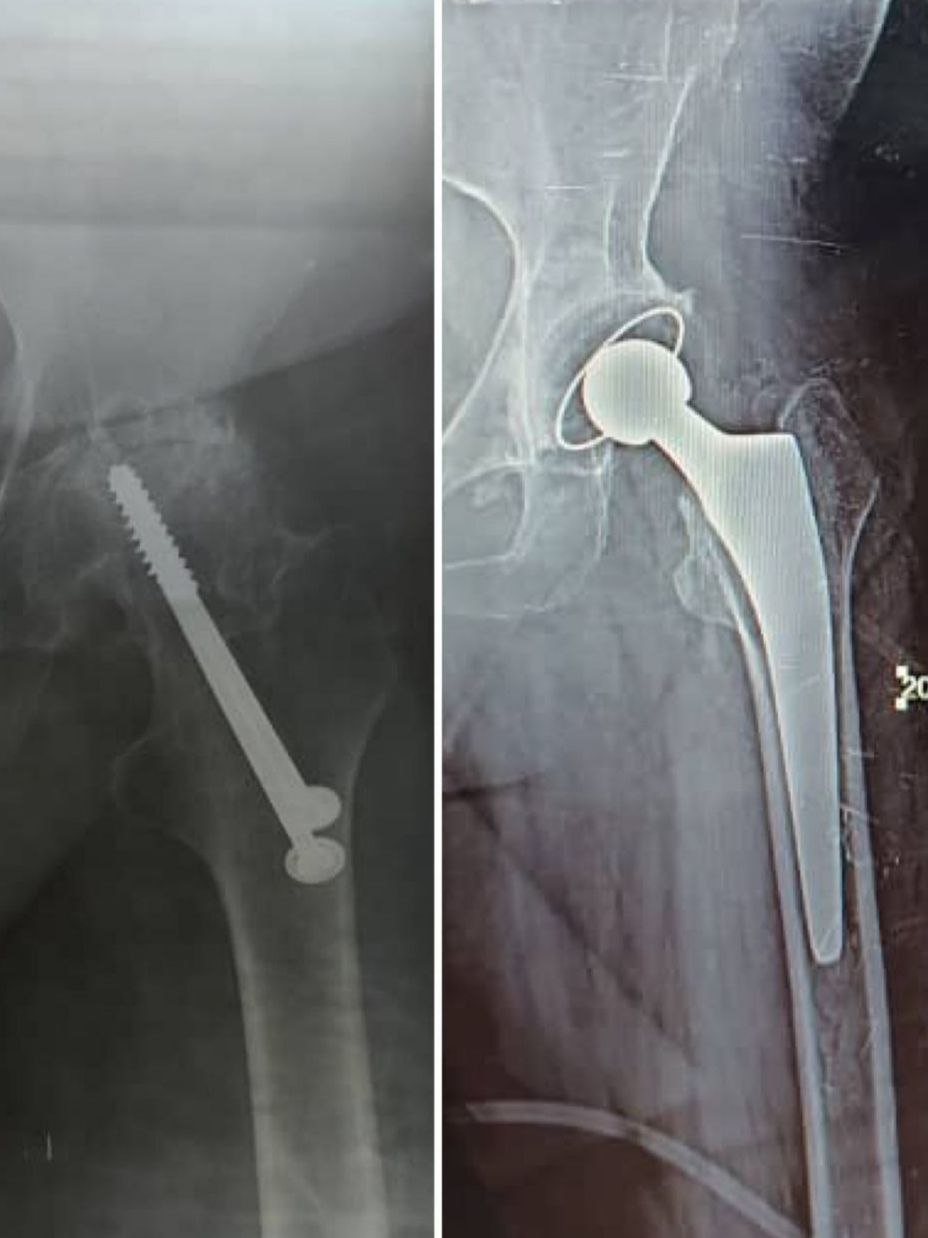

مفصل ورك لا أسمنتي

قبل وبعد تبديل مفصل ورك صناعي مع تطعيم عظمي للعمود الخلفي العلوي بطعم ذاتي من الرأس بتنفيذ دقيق بالتعاون بين شركتنا والدكتور [وليد العبد]. النتيجة: ثبات ممتاز ووضع تشريحي أنيق يعكس جودة العمل ودقة التقنية

مفصل ورك أسمنتي

نموذج لتبديل مفصل ورك إسمنتي لمريضة في العقد السابع تثبت الصورة الشعاعية دقة العمل وقدرات الشركة على تلبية احتياجات الطبيب حيث اجريت العملية في احدى مشافي مدينة منبج واحد اهم جراحين العظمية الدكتور شمس الدين الحسون